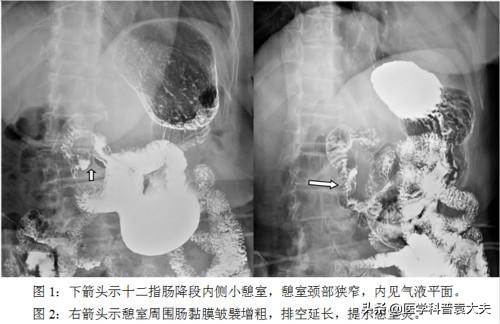

胃、十二指肠、空肠憩室并感染致粘膜糜烂出血;食管裂孔疝引起的粘膜擦伤、嵌顿、绞窄、梗阻、甚或坏疽、穿孔可引起出血;剧烈呕吐使胃内压力骤升可引起食管与胃连接处粘膜撕裂出血。